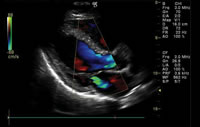

心臓エコー